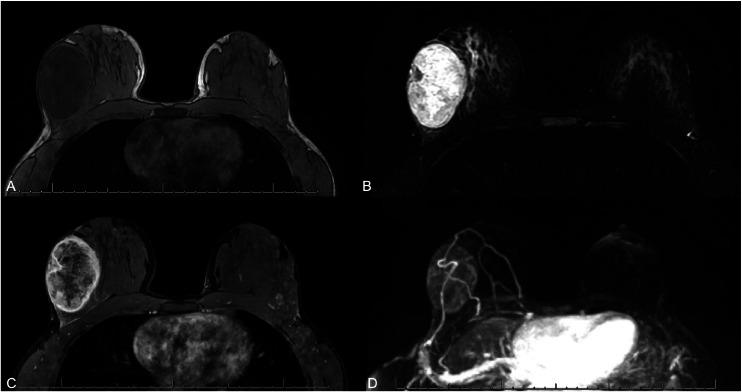

一名15岁女孩患乳腺高级别梭形细胞化生癌。

High-grade spindle cell metaplastic carcinoma of the breast in a 15-year-old girl.

Metaplastic breast cancer in pediatric patients is exceedingly rare with only occasional case reports to present imaging and guide management. Typically diagnosed in patients over 50 years old, metaplastic carcinoma is an aggressive type of breast cancer representing less than 1% of all breast cancers in the United States. To our knowledge, we describe the youngest person to be diagnosed with metaplastic breast cancer in the US. This case underscores the need for clinical vigilance in evaluating rapidly growing breast masses in adolescents. It also emphasizes the value of histopathologic confirmation, even when imaging findings suggest a benign process, to ensure timely diagnosis and management.

小儿患者的化生性乳腺癌极为罕见,仅有零星病例报告用于呈现影像学表现并指导治疗。化生性癌通常在50岁以上的患者中被诊断出来,是一种侵袭性乳腺癌类型,在美国所有乳腺癌中所占比例不到1%。据我们所知,我们描述了美国最年轻的被诊断为化生性乳腺癌的患者。该病例强调了在评估青少年快速生长的乳腺肿块时保持临床警惕的必要性。它还强调了组织病理学确诊的价值,即使影像学表现提示为良性病变,以确保及时诊断和治疗。